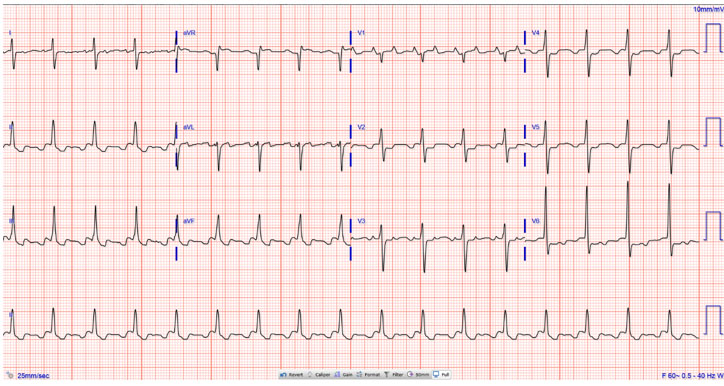

Her complete blood count and electrolytes included a potassium of 3.7 mg/dL, magnesium of 1.8 mg/dL and creatinine of 1.82 mg/dL (baseline 0.8 mg/dL 1 month ago). D-dimer was significantly elevated at 2.24 mg/L FEU (reference range (Ref): >0.65 mg/L FEU). Troponin T was modestly elevated at 0.10 ng/mL (Ref: <0.01 ng/mL). Lactate was elevated at 4.8 mmol/L (Ref: 0.5–2.2 mmol/L). Arterial blood gas revealed pH of 7.31, PCO2 54 mmHg, PCO2 88 mmHg, bicarbonate 26.7 mmol/L, and base excess of 0 mmol/L. SARS-CoV-2 polymerase chain reaction test was negative. Electrocardiogram revealed atrial flutter with variable atrioventricular conduction block which ranged from 3:1 to 5:1. Ventricular rate was consistently bradycardic (Figure 1). The narrow width of the QRS complexes suggests that these are impulses being conducted from a supraventricular origin rather than a ventricular or junctional origin. The morphology of the F waves in II, III, and aVF suggests a clockwise typical flutter. There were no ischemic ST-T segment changes. Her electrocardiogram on admission revealed atrial flutter with HR of 100 bpm (Figure 2). Chest X-ray showed no acute changes. Bedside transthoracic echocardiography showed an ejection fraction of 60% with flattened septum and new signs of right ventricular strain (Figure 3).

Figure 1: 12-Lead electrocardiogram showed atrial flutter at 150 bpm with variable AV conduction. The morphology of the F waves in II, III, and aVF suggests a typical flutter in clockwise direction. The narrow width of the QRS complexes suggests that these are impulses being conducted from a supraventricular origin rather than a ventricular or junctional origin. There were no ischemic ST-T segment changes.

Figure 2: 12 Lead electrocardiogram on admission showed atrial flutter at 100 bpm.